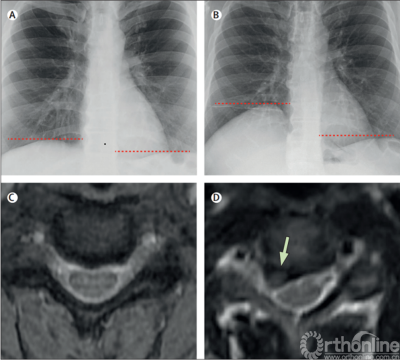

2020年10月Lancet的Clinical picture[2]报道了一例典型的由颈椎病导致呼吸困难的病例。患者是一名50岁男性,突发呼吸短促及右肩后侧疼痛,无任何颈部疼痛、四肢麻木及无力表现。胸部X线提示右侧膈肌抬高(图B),颈椎MRI提示C3- C4椎间盘突出导致右侧C4神经根严重压迫(图D)。在该院行C3-C4的颈椎前路减压融合术(anterior cervical decompression and fusion,ACDF)后,患者的肩痛症状和呼吸困难明显改善。术后随访X线提示患者右侧膈肌恢复到基本正常的高度。

图1:A.2年前胸片. B.术前胸片. C.2年前C3-C4椎间隙MRI. D术前C3-C4椎间隙MRI